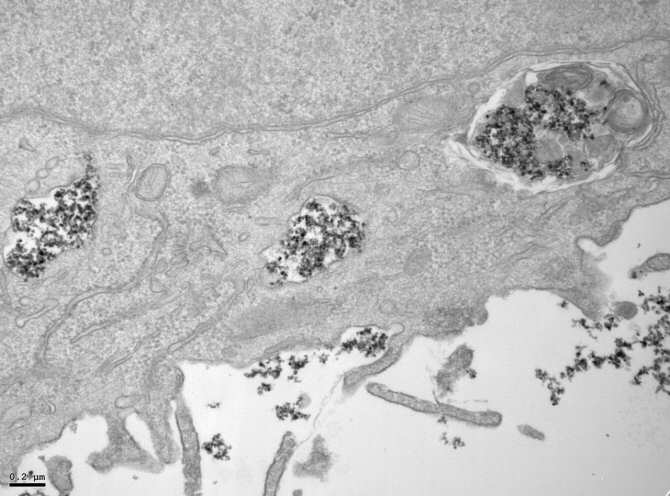

Nanopartículas de óxido de hierro en el interior de vesículas celulares en una imagen tomada con un microscopio electrónico de transmisión (TEM). (Imagen: Yadileiny Portilla / Domingo F Barber / CNB / CSIC)

“En las células tumorales -añade Portilla-, las nanopartículas se acumulan en endolisosomas, donde se degradan más lentamente, mientras que en las células macrofágicas del entorno tumoral, la degradación ocurre más o menos rápidamente dependiendo del recubrimiento, ya que en función de este se acumulan en vesículas con diferente capacidad de degradación. Estos hallazgos son de vital importancia a la hora de diseñar las nanopartículas ya que podremos, en función de su futura aplicación, potenciar el efecto deseado dependiendo de la diana terapéutica”.

El investigador Domingo F. Barber, del Centro Nacional de Biotecnología (CNB), dependiente del CSIC, quien ha liderado el estudio, señala: “Según el tipo de recubrimiento utilizado, cuando las nanopartículas entran en contacto con el entorno biológico se producen diferentes interacciones con las proteínas del medio, afectando a su tamaño final, la vía de captación celular, así como al tránsito que siguen hasta su degradación en la maquinaria celular que se encarga de este proceso (los endolisosomas, un cuerpo del citoplasma celular fundamental para eliminar patógenos o microorganismos)”.